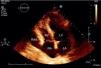

We report the case of a 58-year-old hypertensive man referred for a cardiology consultation due to atypical chest pain. The clinical examination was unremarkable. An electrocardiogram demonstrated sinus rhythm and incomplete right bundle branch block. He had an ambulatory echocardiogram that was described as normal. An exercise test was negative for ischemia and showed intermittent complete right bundle branch block. To exclude coronary disease a contrast computed tomography (CT) scan was performed that revealed a saccular aneurysm of the lateral free wall of the right atrium measuring 45 mm×45 mm×43 mm (Figures 1 and 2). There was no evidence of coronary disease. Given the CT findings, transthoracic echocardiography was repeated and revealed a cystic, pulsatile structure in continuity with the free wall of the right atrium through a narrow neck (Figure 3) permitting low-speed two-way flow, subsequently confirmed by injection of Sonovue® contrast. No cardiac thrombi were visualized. The tricuspid valvular apparatus and right ventricle were morphologically normal, as was biventricular systolic function. Similar findings were visualized on the transesophageal echocardiogram.